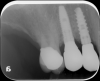

The presence of dark spaces, even from a cross-sectional photographic view, may indicate that an aftermarket part was used (Figure 13). Radiographically, everything should appear intimately tight against the implant interface (Figure 14). A visually absent intimate connection may indicate that the abutment/restoration and implants are incompatible (Figure 15).

Fig 15. Radiographic view of an implant restoration at tooth No. 29; the abutment/restoration sits on the very edge of the implant collar and is clearly not made for that platform.

Figure 15